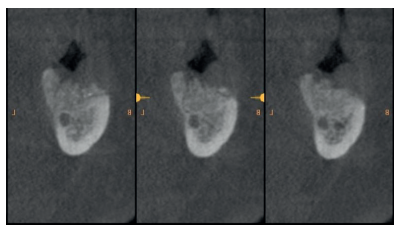

Al quinto mes se realizó un CBCT de control, para evaluar la homogeneidad en la zona y se planificó la colocación de un implante corto de 5 x 6 mm de Proclinic® (Figura 9) al mismo tiempo que fue tomada una biopsia de la zona. Se procedió a inyectar la misma anestesia que en la primera cirugía, se elevó un colgajo a espesor total y se tomó una biopsia con trefina de 3.5 mm de la zona injertada (Figura 10). En la misma zona donde fue realizada la toma de biopsia, sin pasar ninguna otra fresa, se colocó el implante empleándolo como expansor, de modo que se condensasen las paredes que rodeaban al implante (Figura 11).